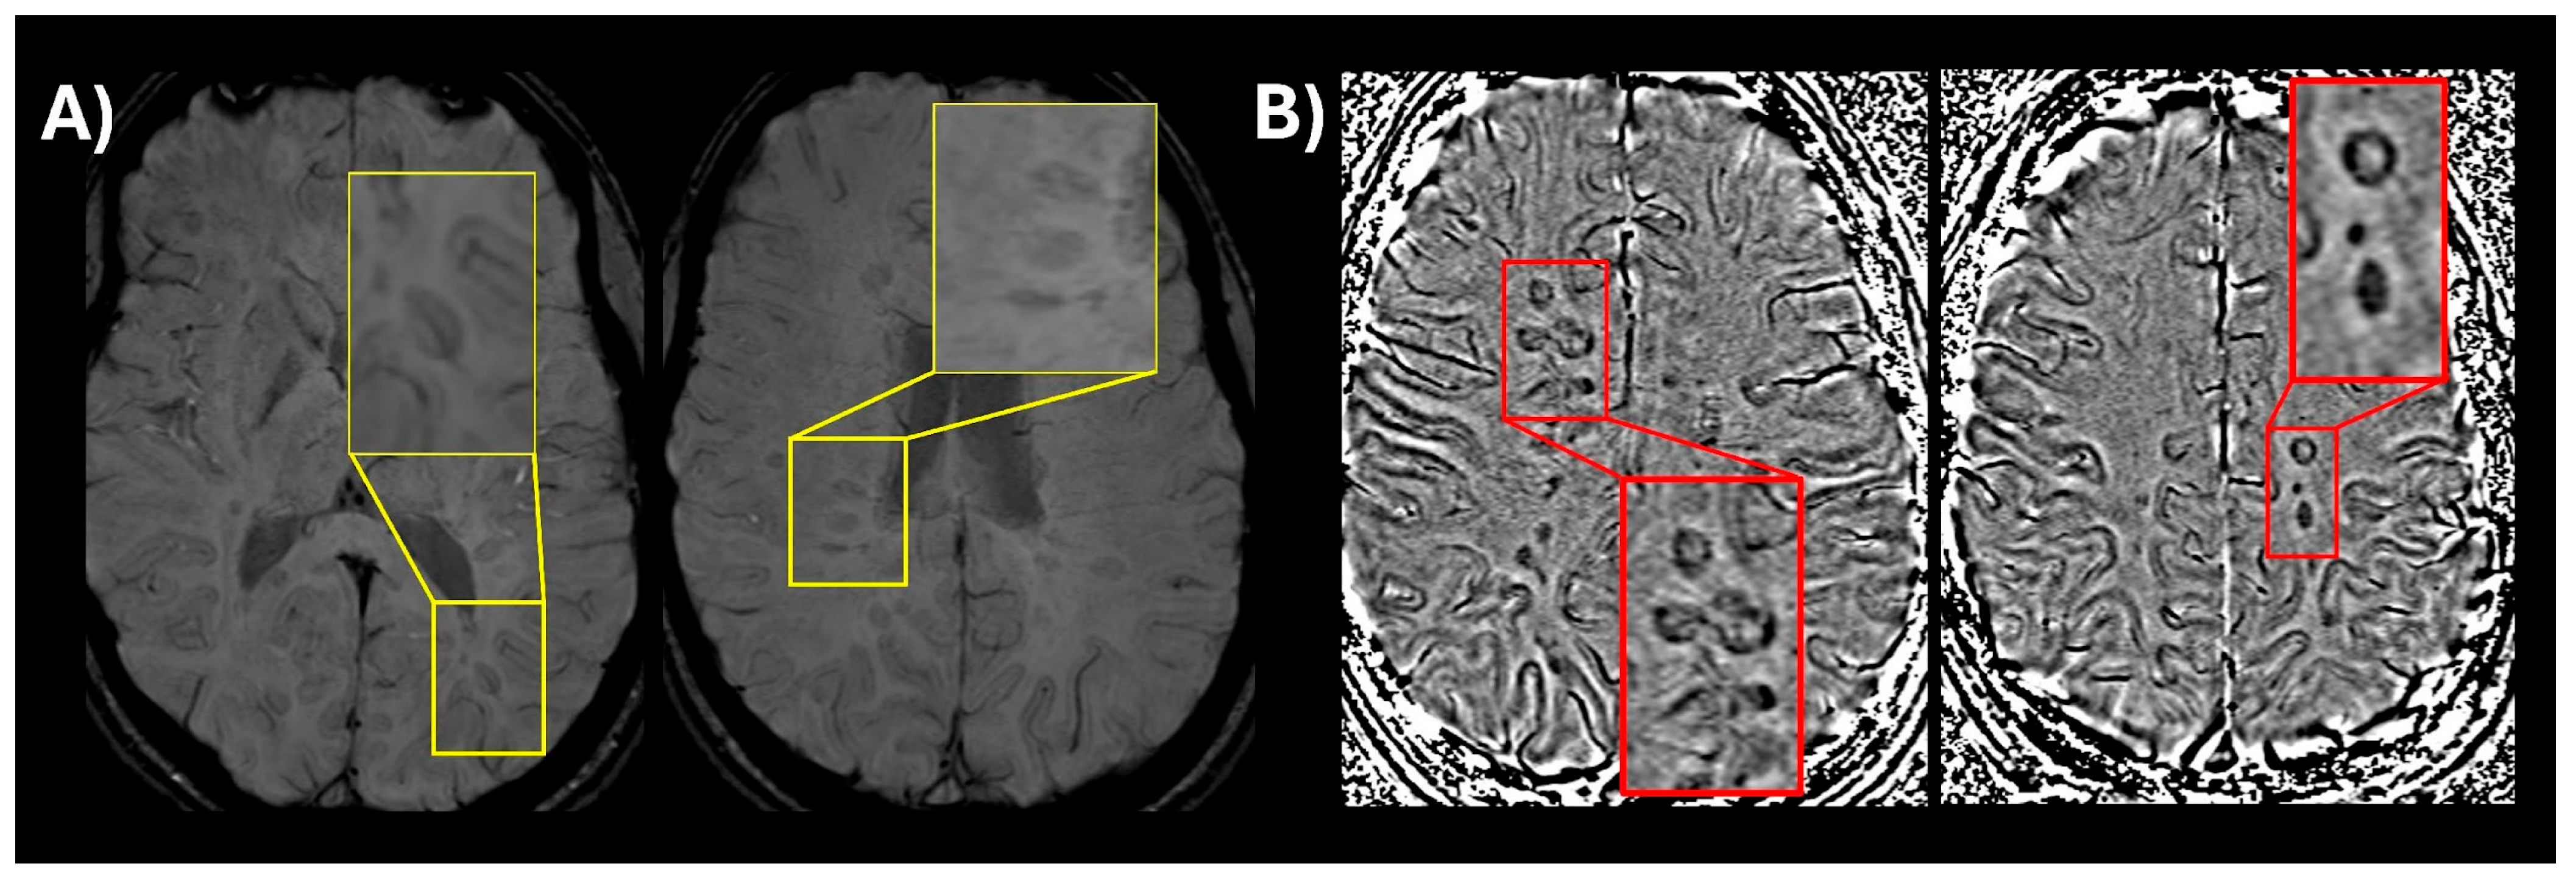

- Sati, P.; George, I.C.; Shea, C.D.; Gaitán, M.I.; Reich, D.S. FLAIR*: A combined MR contrast technique for visualizing white matter lesions and parenchymal veins. Radiology 2012, 265, 926–932. [Google Scholar] [CrossRef]

- Sati, P.; Oh, J.; Constable, R.T.; Evangelou, N.; Guttmann, C.R.G.; Henry, R.G.; Klawiter, E.C.; Mainero, C.; Massacesi, L.; McFarland, H.; et al. The central vein sign and its clinical evaluation for the diagnosis of multiple sclerosis: A consensus statement from the North American Imaging in Multiple Sclerosis Cooperative. Nat. Rev. Neurol. 2016, 12, 714–722. [Google Scholar] [CrossRef] [PubMed]

- Solomon, A.J.; Schindler, M.K.; Howard, D.B.; Watts, R.; Sati, P.; Nickerson, J.P.; Reich, D.S. “Central vessel sign” on 3T FLAIR* MRI for the differentiation of multiple sclerosis from migraine. Ann. Clin. Transl. Neurol. 2016, 3, 82–87. [Google Scholar] [CrossRef]

- Castellaro, M.; Tamanti, A.; Pisani, A.I.; Pizzini, F.B.; Crescenzo, F.; Calabrese, M. The use of the central vein sign in the diagnosis of multiple sclerosis: A systematic review and meta-analysis. Diagnostics 2020, 10, 1025. [Google Scholar] [CrossRef] [PubMed]

- Toljan, K.; Daboul, L.; Raza, P.; Martin, M.L.; Cao, Q.; O’Donnell, C.M.; Rodrigues, P.; Derbyshire, J.; Azevedo, C.J.; Bar-Or, A.; et al. Diagnostic performance of central vein sign versus oligoclonal bands for multiple sclerosis. Mult. Scler. J. 2024, 30, 1268–1277. [Google Scholar] [CrossRef] [PubMed]

- Toljan, K.; Amin, M.; Ontaneda, D. Central vein sign and paramagnetic rim lesion abbreviated counting methods for diagnosis of multiple sclerosis: A systematic review and meta-analysis. Clin. Radiol. 2025, 88, 106984. [Google Scholar] [CrossRef]